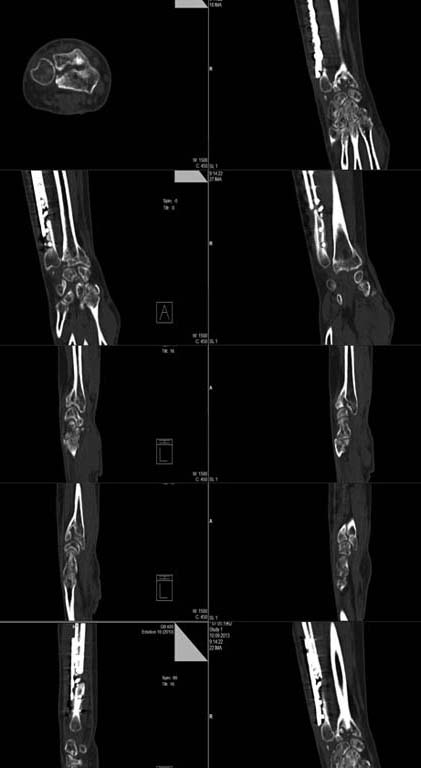

КТ

По простым снимкам (а по КТ еще лучше) видно, что суставная поверхность отклонена к тылу, кисть на подвывихе, есть внутрисуставная деформация. Укорочение локтевой кости только усилило проблемы, а тут еще и несращение...

Word, 149 Kb

Случай сложный и наверняка здесь действует несколько механизмов формирования боли. Это и ложный сустав локтевой кости, и тыльный подвывих кисти (хорошо виден на срезе КТ, обозначенном стрелкой), и нарушения в лучелоктевом сочленении, в т.ч., за счет не полностью и со смещением сросшегося дорсального фрагмента лучевой кости, и сужение карпального канала за счет смещения кисти к тылу. Поэтому, вмешательство на лучевой кости должно предполагать не только ее укорочение, но и коррекцию наклона суставной поверхности за счет разворота ладонного фрагмента (клиновидная остеотомия) и сопоставление его с тыльным фрагментом, для чего, вероятнее всего, понадобится разрушение имеющегося в области метадиафиза сращения тыльного и ладонного фрагментов. Во вложенном файле случай хотя и не идентичный, но похожий (5 лет после травмы). Боли и проявления синдрома карпального канала прошли только через 10-12 месяцев после операции.

Сросшийся со смещением перелом лучевой кости через 3 месяца после травмы лечить укорачивающей остеотомией локтевой кости конечно дикость и в корне не правильно. Для определения объема и тактики лечения необходимо узнать что именно от руки хочет сама пациентка, какая функция её будет устраивать. На данном этапе, моё мнение, нужно прежде всего решать вопрос с ложным суставом локтевой кости. Подвывиха кисти на рентгенограммах и КТ я не вижу, данные изменения называются "адаптивным запястьем". Это всегда развивается при тыльном наклоне суставной поверхности лучевой кости, в следствии которого полулунная кость разворачивается в ладонную сторону. Касаемо дистального луче-локтевого сочленения: не понятно что именно вас не устраивает, если дисконгруетность суставных поверхностей, то при небольших сроках после травмы лучше это исправлять за счет остеотомии лучевой кости, если проблемы со связочным аппаратом, то делать пластику связок. И мне кажется эти манипуляции нужно перенести на второй этап, от который при успехе первого больная скорее всего откажется, т.к. функция кисти при таких смещениях не редко устраивает пациентов. Но все нужно решать индивидуально.